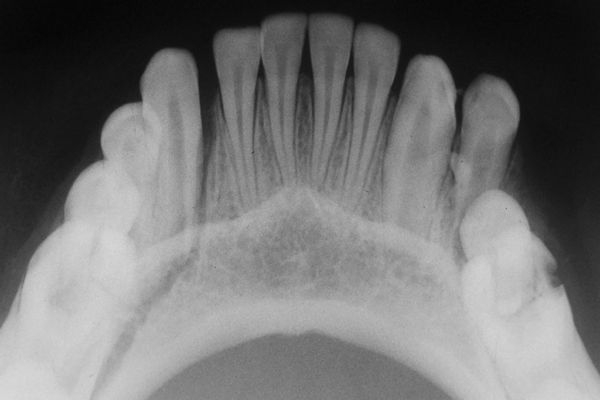

Рентгенография небного шва: Медицинские исследования и диагностика

Раздел: Фотопутеводитель